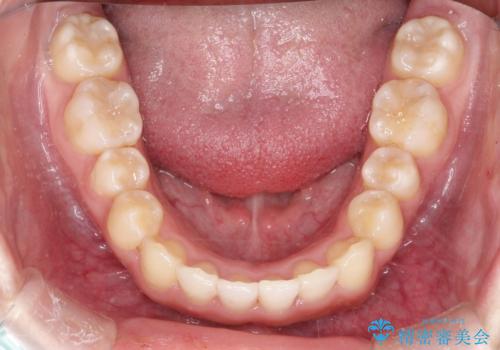

インビザラインでの前歯のガタガタの矯正

- 上下の前歯のがたつきを主訴に来院されました。

歯と歯の間をわずかに削りスペースを作り、インビザラインにて矯正治療を行うこととしました。

使用時間を守っていただけたので、スムーズに矯正を終了することができました。